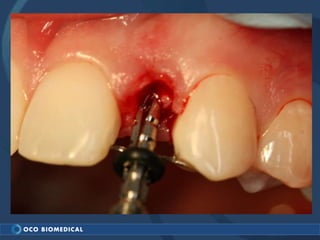

A 3.0mm dental implant was placed to replace congenitally missing maxillary lateral incisors. Dr. Tim Kosinski used a 1.8mm pilot bur and tissue punch to prepare the osteotomy site, then placed the implant by hand and seated it with a torque wrench. After ensuring the implant trajectory was within the restorative envelope, an acrylic coping was placed for temporary fabrication. At the 1 week post-op appointment, excellent soft tissue response and papilla formation were observed, and a final impression was taken to send to the lab for crown fabrication.